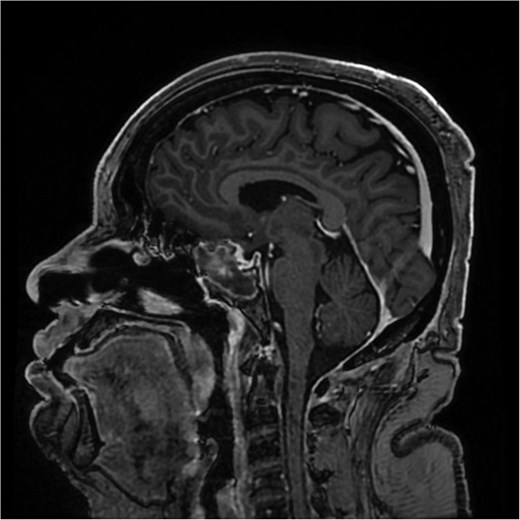

The initial evaluation included a brain magnetic resonance imaging (MRI), showing a small pituitary mass measuring 1.3 × 2.1 × 1.9 cm with suprasellar extension, neighboring the optic chiasm (Figs 1 and 2). Laboratory results revealed a high prolactin level of 110 ng/ml and normal thyroid function tests. A pituitary macroadenoma, specifically a prolactinoma, was presumed, and cabergoline was initiated.

A coronal brain MRI showing a heterogeneous, enhancing lesion located within the sphenoid sinus, extending superiorly to the sellar and parasellar regions. The mass shows irregular borders and appears to cause a mild compression of the optic chiasm.